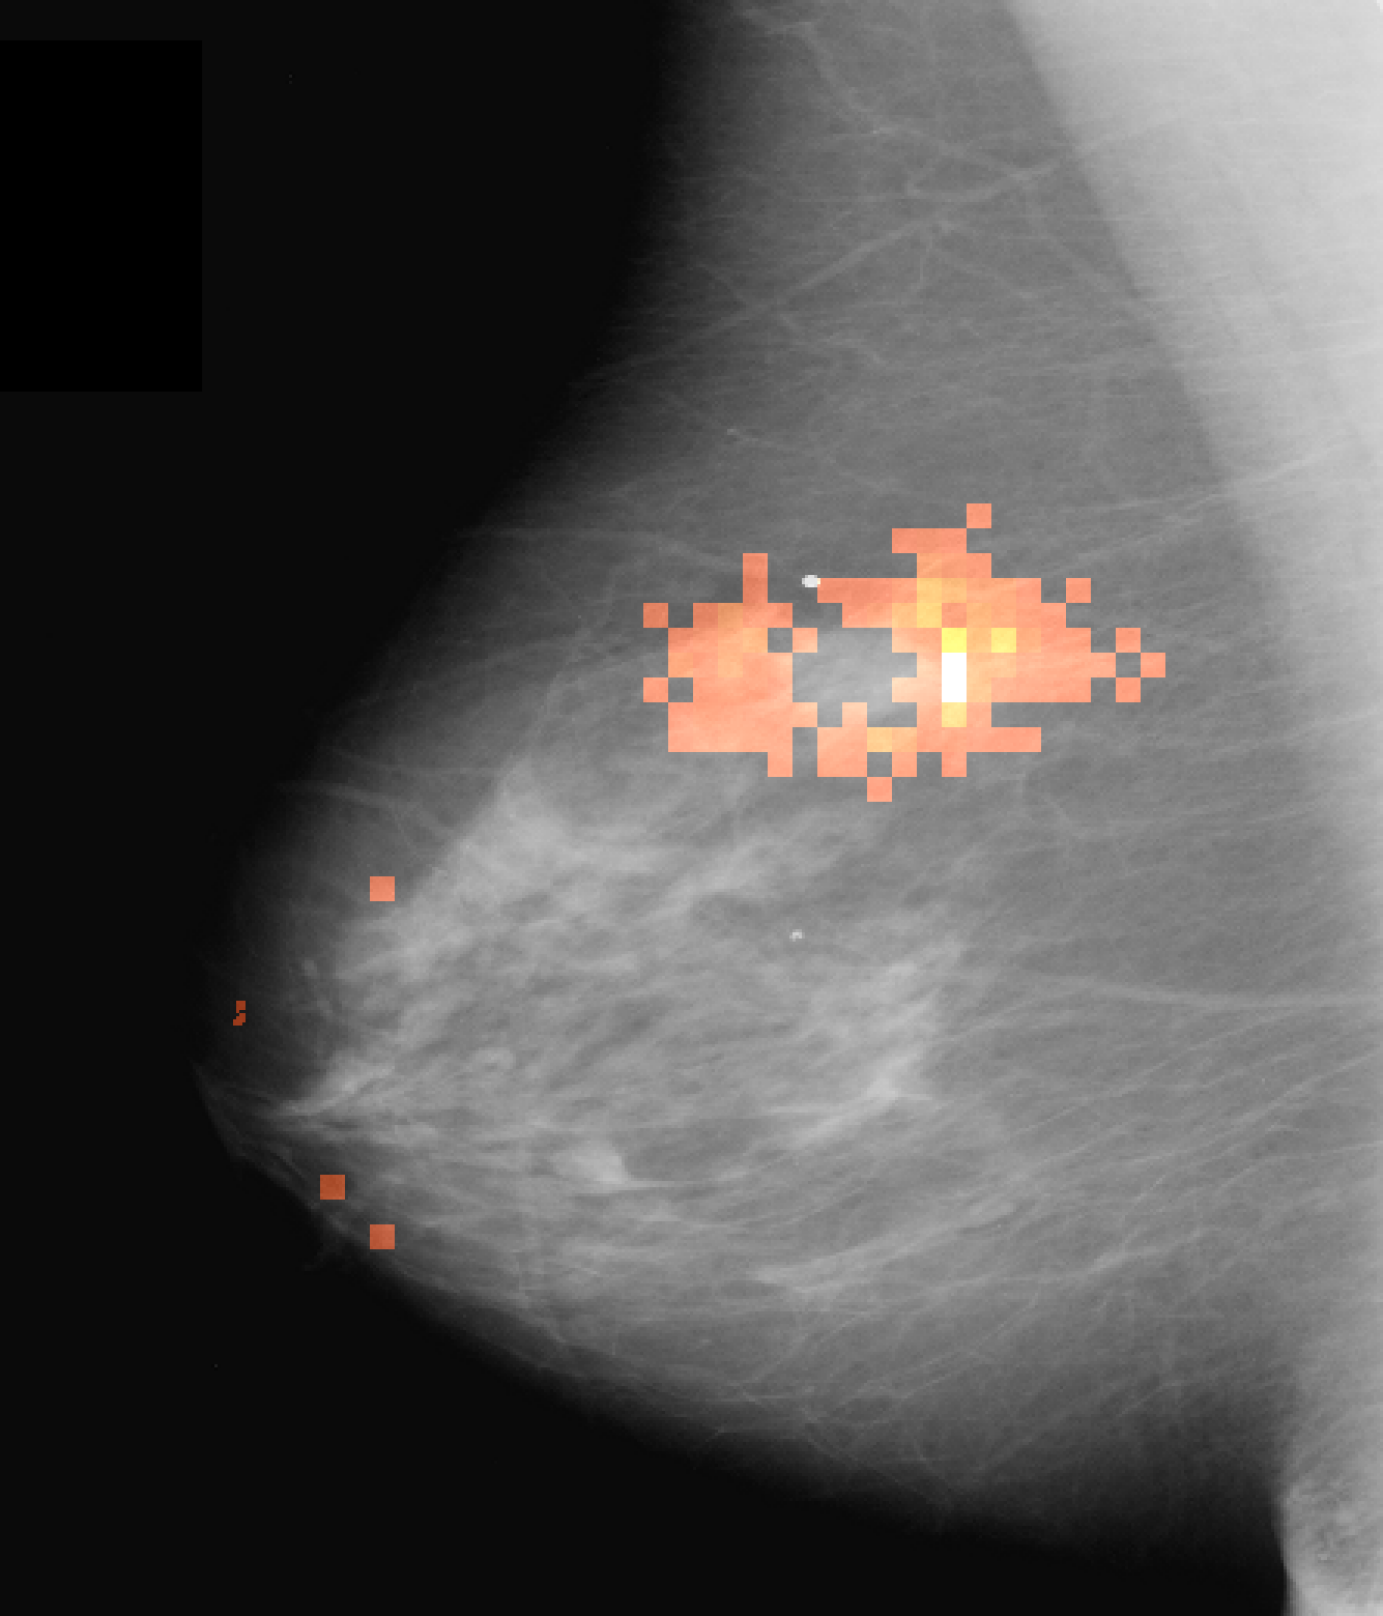

Qualitatively, as depicted in Fig. 3 (b), our salient regions appear at the circumference of masses which is reasonable w.r.t. the fact that this is the discriminative region for the presence of masses. This is in line with [16], which reports on injection of poorly circumscribed, malignant looking masses while transforming healthy cases into pathological ones using a GAN variant. In addition, our method yields more accurate visualizations than CAM and SAL (Fig. 3 first row), i.e. it has a smaller, more precise and more informative feature attribution than these standard visualization methods (Fig. 3 (b)-(d)).